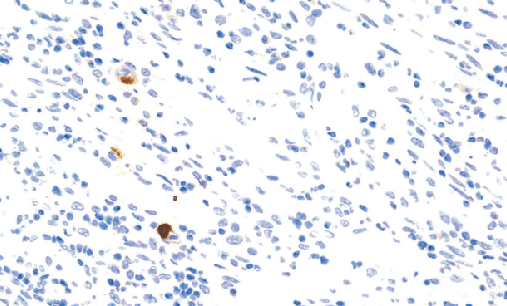

Herpes Simplex Virus Il(HSV I)免抗人2型单纯疤疹病毒多克隆抗体

单纯疯疹病毒2型(HSV2)是一种疯疹病毒,疯疹病毒还包括单纯疯疹病毒(HSV1),EB病毒(EBV)和水痘-带状疹病毒(水痘)。HSV1和HSV2的区分非常困难。完整病毒由核心、衣壳、被膜(Tegument)及囊膜组成核心含双股DNA,缠绕成纤丝卷轴。衣壳呈二十面体对称。这些病毒能够进人一个潜在阶段机体没有明显的感染迹象和传染水平变得很低,潜伏期的病毒DNA再整合到宿主细胞基因组中。

- 阳性部位:胞质,胞核

- 适用组织:石蜡切片

- 预处理:热修复